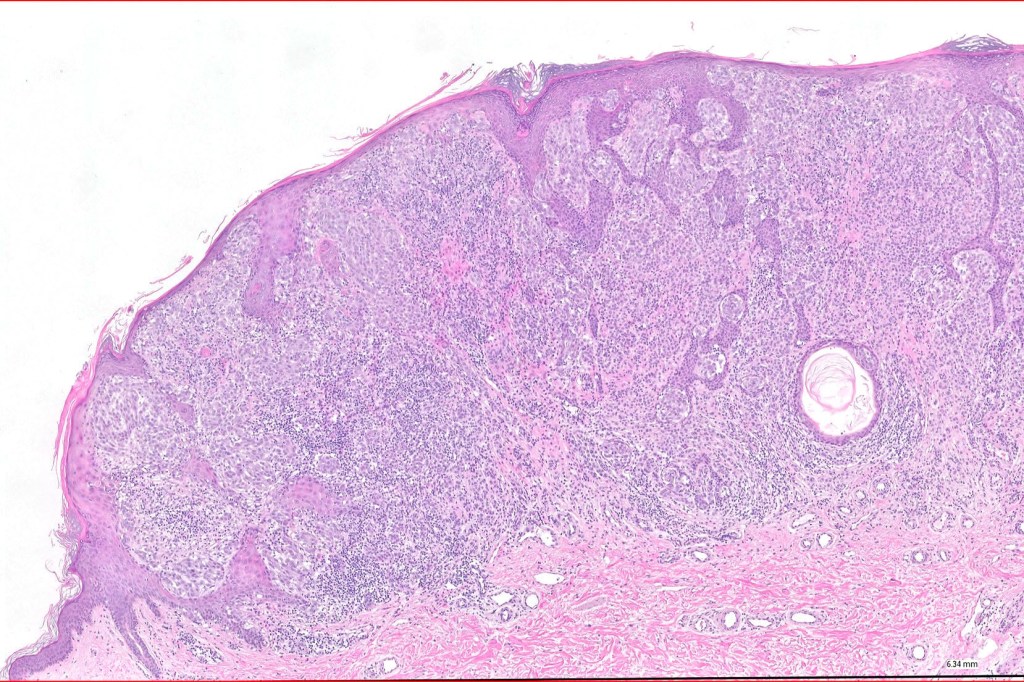

Histological features

•>5-10 mm

•Involve deep dermis or subcutis

•Asymmetrical, poorly circumscribed

•May show effacement/consumption of epidermis or ulceration

•Peripheral Pagetoid spread

•Large nodules which often show impaired maturation